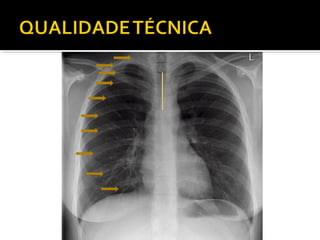

Este documento fornece parâmetros técnicos para realizar uma radiografia de tórax, incluindo posicionamento correto do paciente, dose adequada de radiação e estruturas anatômicas a serem avaliadas, como coração, pulmões, pleura, diafragma e ossos do tórax.